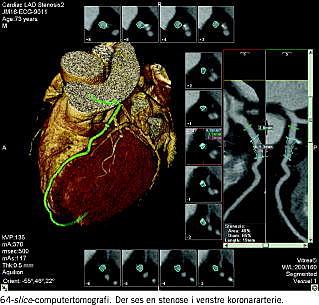

Den nyeste udvikling inden for multi slice -computertomografi (CT)-teknik (MSCT) tyder på, at MSCT vil kunne opfylde fremtidens krav til undersøgelsesmetode hos patienter med formodet åreforkalkning i kranspulsårerne [1, 2]. Ved MSCT får man mulighed for både at vurdere, om der er stenose af kranspulsårene og i givet fald graden af stenose samt hvilken type af stenose der er tale om, og om der er forkalkede plaques eller fibrøse/fedtholdige plaques i karrene. Moderne CT-teknologi med MSCT findes nu kommercielt tilgængelig som såkaldte 64-slice -skannere, som allerede står på enkelte radiologiske afdelinger i Danmark. Hermed opnås der mulighed for meget hurtig CT (ca. ti sekunder), og med disse skannere sikres god billedopløselighed i alle planer modsat de gamle skannere, som har maksimal opløslighed i x-y-retningen, men som ikke kan rekonstruere med den samme opløslighed i z-retningen. Denne markant forbedrede rumlige opløselighed med MSCT giver mulighed for højkvalitets-CT-angiografiske undersøgelser, hvis kvalitet nærmer sig kvaliteten af den klassiske invasive arteriografi. Det er derfor naturligt, at man ved en række problemstillinger, som kræver billeddiagnostisk udredning, fremover kan forvente, at den initiale udredning vil ske med CT efter injektion af røntgenkontrast. Efter skanningen er der billedbehandling på en arbejdsstation, og man forsøger at automatisere billedbehandlingen så meget som muligt. Med 64-slice -CT kan undersøgelsen af patienten gennemføres i løbet af 15 minutter. Der er ingen patientforberedelse. Det er dog nødvendigt med sammenlignende undersøgelser af CT-KAG og KAG for endeligt at kunne evaluere den nye metodes validitet [1, 2]. Desuden er det nødvendigt med nærmere undersøgelse af den stråledosis, som patienten udsættes for i forhold til KAG. Patienterne kan dog ikke behandles ved hjælp af CT-skanneren, så der vil fortsat være behov for invasiv KAG, når man skal foretage ballondilatation og anlæggelse af stent i krononararterierne. Overordnet rummer den nyeste CT-teknologi en mulighed for en forskydning fra invasive diagnostiske procedurer til en for patienterne mere skånsom undersøgelse, og samtidig sikres yderligere forbedring af billedkvalitet og den diagnostiske sikkerhed (Figur 1 ).